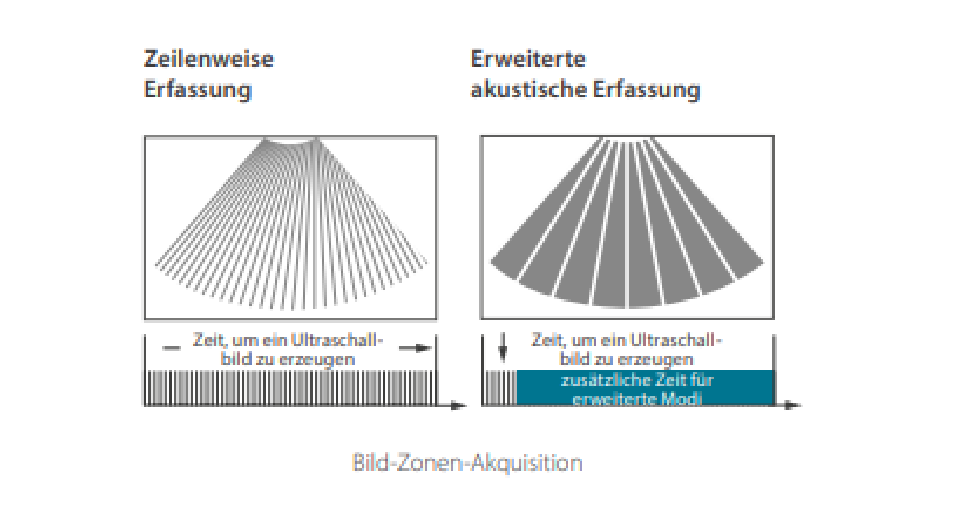

Dank der ZONE Sonography?-Technologie (ZST+) wird das B-Bild des Resona 7 ├╝ber die komplette Tiefe fokussiert, sodass keine Fokuspunkte mehr gesetzt werden m├╝ssen. Die Schall-Lauf-Geschwindigkeit (SSC) wird auf Knopfdruck individuell auf den Patienten angepasst, was die Darstellung von Organen, Grenzfl?chen und Gewebever?nderungen erheblich verbessert. Und dank der fortschrittlichen iFusion-Funktion k?nnen optional die Daten von Ultraschall-, MRT-und CT-Bildern synchronisiert werden.